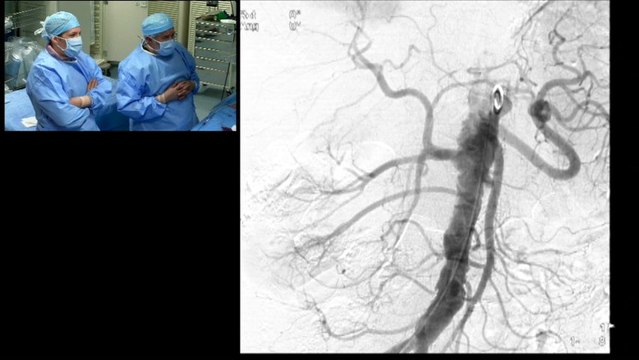

bilateral, internal, mammary, artery, graft, angiogram, radial, approach, incathlab